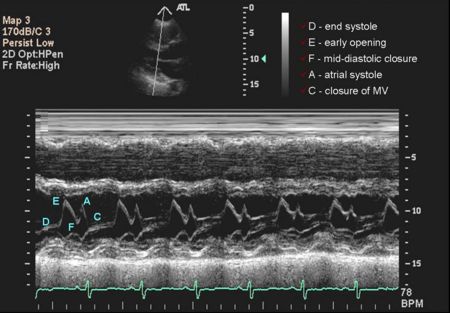

Mitral Valve M-mode Analysis

- Anterior leaflet with E/A appearance of diastology

- Decreased EF slope in MS

- Scalloping of leaflet tip in end systole in prolapse

M Mode in Mitral Stenosis

- Leaflet tips bright (calcified) and thickened

- E/F slope decreased